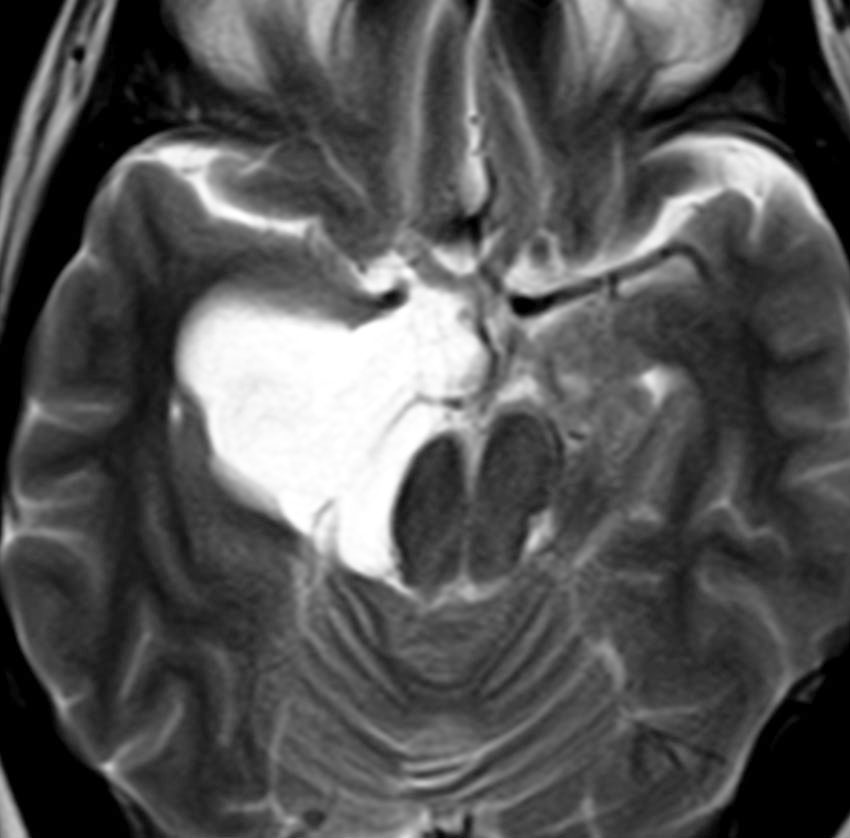

多くは側脳室の中にみつかります。丸いものや楕円形のものがあります。これも脳腫瘍と間違われることがあるのですが,脈絡叢にくっつく位置にあって,内部が髄液であることで区別できます。脳室内脈絡叢のう胞と脳室内くも膜のう胞は区別できませんが,両方ともほっておけばいいので心配ありません。

choroidplecyst側脳室三角部によくみられる両側性の脈絡叢のう胞です。成人女性にみられたものです。左右の大きさが違うこともありますし,脈絡叢がある部位ならどこでも発生するものです。脳室内くも膜のう胞と区別できないようなものもあります。